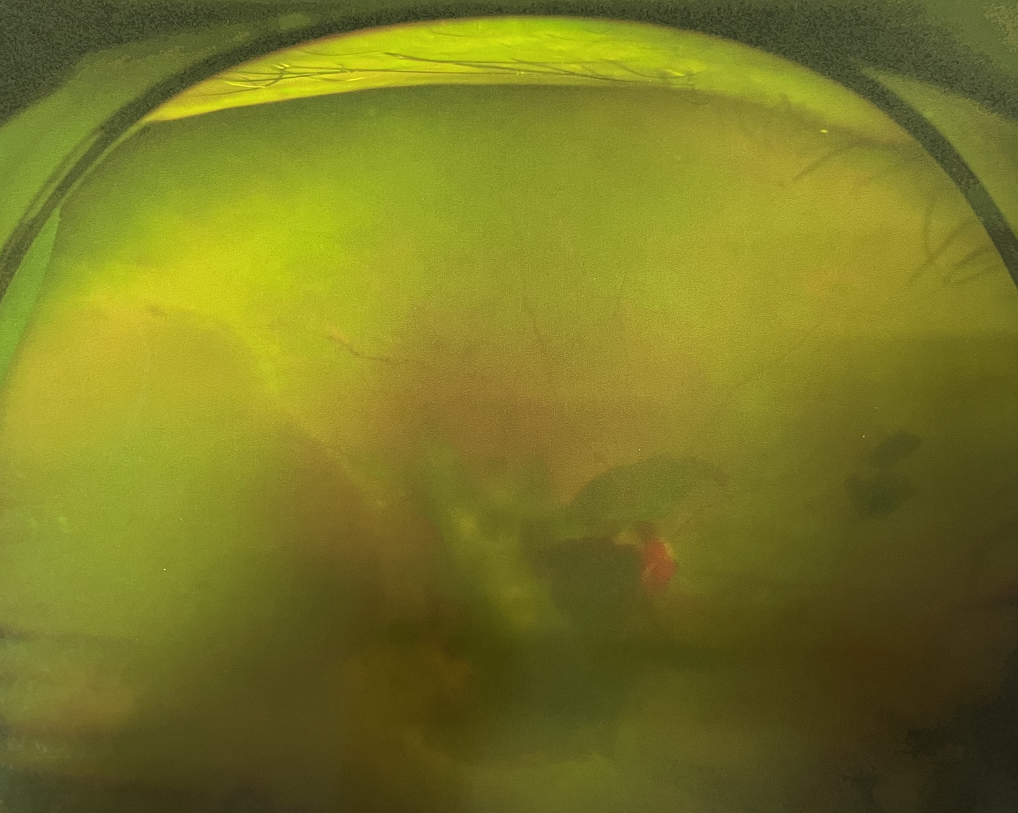

眼底出血雖然“看不見(jiàn)”,但嚴(yán)重可致盲!

眼底出血不是獨(dú)立的眼病,而是由于眼球自己的病變和某些全身疾病的并發(fā)癥導(dǎo)致眼底的視網(wǎng)膜或脈絡(luò)膜出血,如果出血量大就會(huì)進(jìn)入到眼球的玻璃體內(nèi),從而影響視力,如果沒(méi)有得到恰當(dāng)?shù)闹委熆蓭?lái)更嚴(yán)重的并發(fā)癥造成失明。

眼底出血的患者,如果出血量少,而且在視網(wǎng)膜周邊部可能沒(méi)有明顯癥狀,患者僅感到眼前有黑影浮動(dòng);如出血量多,將嚴(yán)重影響視力,甚至完全被黑影所遮擋僅剩光感;如出血位于視網(wǎng)膜的黃斑區(qū),患者視野中心區(qū)被暗影遮擋,周邊尚有部分視力。

先是散瞳檢查眼底,可以明確眼底出血的性質(zhì),出血部位和出血量有多少。眼B超檢查,對(duì)于眼底出血量特別多,無(wú)法看清眼底的患者,就需要進(jìn)行眼部B超檢查,以了解出血量,出血部位、有無(wú)合并視網(wǎng)膜脫離;還可以明確是否患有視網(wǎng)膜或脈絡(luò)膜的腫瘤。

眼底血管熒光造影是非常重要的一種檢查手段。這個(gè)檢查對(duì)于眼底視網(wǎng)膜的血管有無(wú)滲漏、出血、新生血管生長(zhǎng)、無(wú)灌注區(qū)等可以清晰展現(xiàn);而且可以對(duì)視神經(jīng)炎和缺血性視神經(jīng)病變予以鑒別。

眼底彩色照相、眼部OCT掃描也是近來(lái)在眼底病中應(yīng)用較多的一種無(wú)創(chuàng)、快速、可重復(fù)的檢查手段,檢查結(jié)果可靠、一目了然。